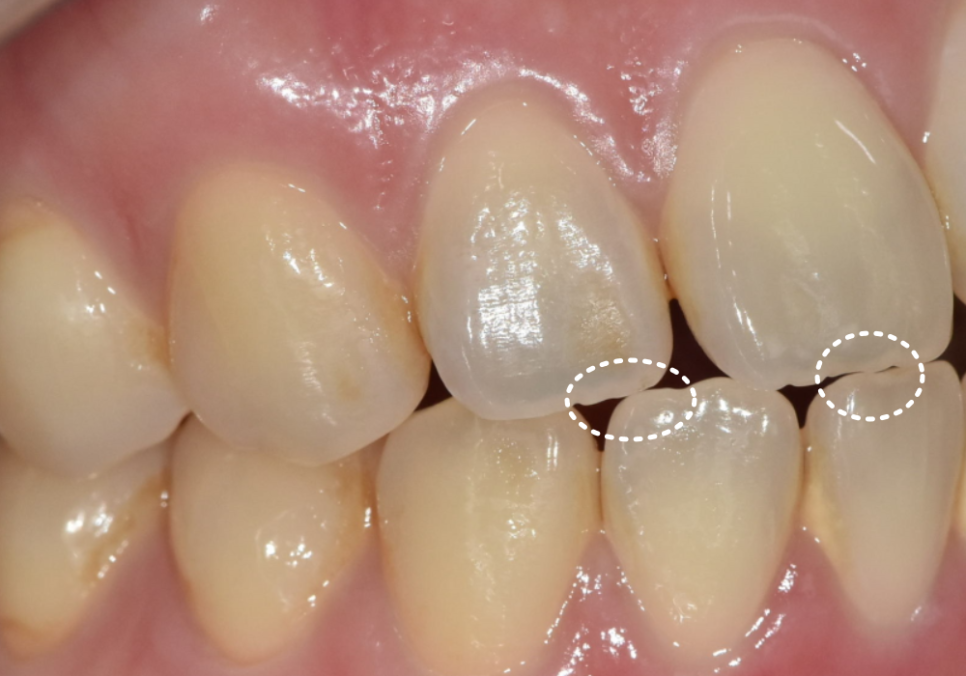

라미네이트가 오래 버티려면

앞니끼리 정면충돌하지 않도록 만드는 것이 핵심입니다.

그래서 아주 얇은 여유 공간을 만들어 주는 것이 중요했습니다.

250403

저희 병원의 강점인 원내 기공소를 통해

기공사와 바로바로 소통하며

· 앞니 돌출감을 얼마나 줄일지

· 길이를 어떻게 맞출지

· 힘이 덜 받는 각도를 어떻게 잡을지

이런 요소들을 실제 구강 상황과 비교해

즉각적으로 조정할 수 있었습니다.

250410 절단교합으로 인한 앞니 레진 깨짐, 교정 없이 해결한 사례

단순히 “예쁘게 만드는 라미네이트”가 아니라

파절 위험을 낮추는 기능적 디자인으로

완성된 것이죠.